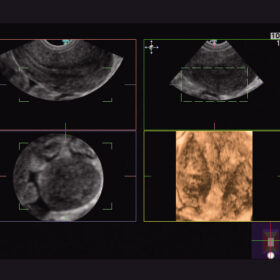

Ultrasound Aloka Prosound Alpha 6 – Image Gallery and Videos

Confident Observations and Measurements For Both Mother and Child

- Spatio-temporal Image Correlation (STIC)

- Dynamic Slow-motion Display (DSD)